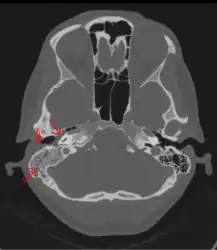

The diagnosis of mastoiditis is clinical—based on the medical history and physical examination. Imaging studies provide additional information; The standard method of diagnosis is via MRI scan although a CT scan is a common alternative as it gives a clearer and more useful image to see how close the damage may have gotten to the brain and facial nerves. Planar (2-D) X-rays are not as useful. If there is drainage, it is often sent for culture, although this will often be negative if the patient has begun taking antibiotics. Exploratory surgery is often used as a last resort method of diagnosis to see the mastoid and surrounding areas.[7][8]

Acute mastoiditis

CT scan: Otitis media (simple arrow) and mastoiditis (double arrow) of the right side (left side in image). The external auditory canal is partially occupied by suppuration (triple arrow). 44-year-old woman